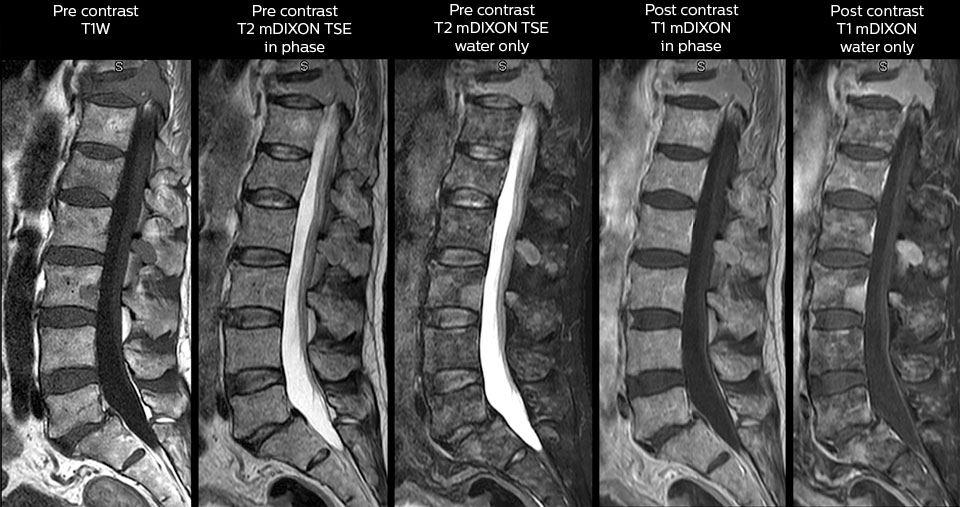

To minimize the time taken to perform scans, rapid MRI examination protocols (ExamCards) were developed, shortening the total scanning time to even less than 10 minutes in some exams. Techniques like mDIXON (modified DIXON) are used for robust capturing of fat-free MRI images in a hectic ED environment.

Including mDIXON TSE for robust fat suppression

“We use mDIXON TSE extensively in our spine imaging in the emergency room,” says Dr. Karis. “It’s particularly nice in that it is very robust with regard to susceptibility type of problems that would come up with traditional spectral fat-saturated images; these problems are essentially eliminated with the mDIXON technique. In our ED environment it’s really nice to have the fat-free imaging that goes along with the mDIXON technique.

“For the thoracic and cervical spine routine non-contrast exam, for example, we perform one mDIXON T2 TSE sequence, which provides us with two outputs: the fat-and-water-together T2-weighted images, as well as the water-only sagittal T2-weighted images. And then we also perform an axial gradient echo exam.”